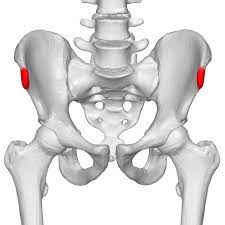

It provides attachment for the inguinal ligament , the sartorius muscle , 1 4 and the tensor fasciae latae muscle. The anterior superior iliac spine (asis) is the most anterior part of the iliac crest. An anterior superior iliac spine (asis) avulsion is a traumatic avulsion of the asis due to a sudden and forceful contraction of the sartorius and tensor fascia lata that occurs in young athletes. Asis, anterior superior iliac spine. This part is the most observable and palpable of the pelvis. The posterior border of the ala, shorter than the anterior, also presents two projections separated by a notch, the posterior superior iliac spine and the posterior inferior iliac spine. Diagnosis is made radiographically with displaced injuries but ct/mri may be required to diagnosis nondisplaced fractures. It provides attachment for the inguinal ligament, and the sartorius muscle. An anterior inferior iliac spine (aiis) avulsion is an apophyseal avulsion injury seen in adolescent athletes as a result of eccentric contraction of the rectus femoris. It refers to the anterior extremity of the iliac crest of the pelvis. The anterior superior iliac spine refers to the anterior extremity of the iliac crest of the pelvis. Outer lip of anterior iliac crest, anterior superior iliac spine (asis) insertion: Classification four types of coccyx have been described:

Outer lip of anterior iliac crest, anterior superior iliac spine (asis) insertion: Aug 29, 2017 · aiis, anterior inferior iliac spine; Asis, anterior superior iliac spine. The posterior border of the ala, shorter than the anterior, also presents two projections separated by a notch, the posterior superior iliac spine and the posterior inferior iliac spine. An anterior superior iliac spine (asis) avulsion is a traumatic avulsion of the asis due to a sudden and forceful contraction of the sartorius and tensor fascia lata that occurs in young athletes. The tensor fasciae latae and sartorius muscles of the thigh have their origins at the anterior superior spine. An anterior inferior iliac spine (aiis) avulsion is an apophyseal avulsion injury seen in adolescent athletes as a result of eccentric contraction of the rectus femoris. It provides attachment for the inguinal ligament, and the sartorius muscle. The posterior superior iliac spine serves for the attachment of the oblique portion of the posterior sacroiliac ligaments and the multifidus. It provides attachment for the inguinal ligament , the sartorius muscle , 1 4 and the tensor fasciae latae muscle. It can be palpated by putting the hands at the top of the hipbones and following the bony margins toward the front of the hips. Classification four types of coccyx have been described: Diagnosis is made radiographically with displaced injuries but ct/mri may be required to diagnosis nondisplaced fractures.

The blog post articles in this. Outer lip of anterior iliac crest, anterior superior iliac spine (asis) insertion: The anterior superior iliac spine is a bony projection of the iliac bone, and an important landmark of surface anatomy. The tensor fasciae latae muscle attaches to the lateral aspect of the superior anterior iliac spine, and also about 5 cm away at the i. Thigh abduction, thigh internal rotation (anterior part);